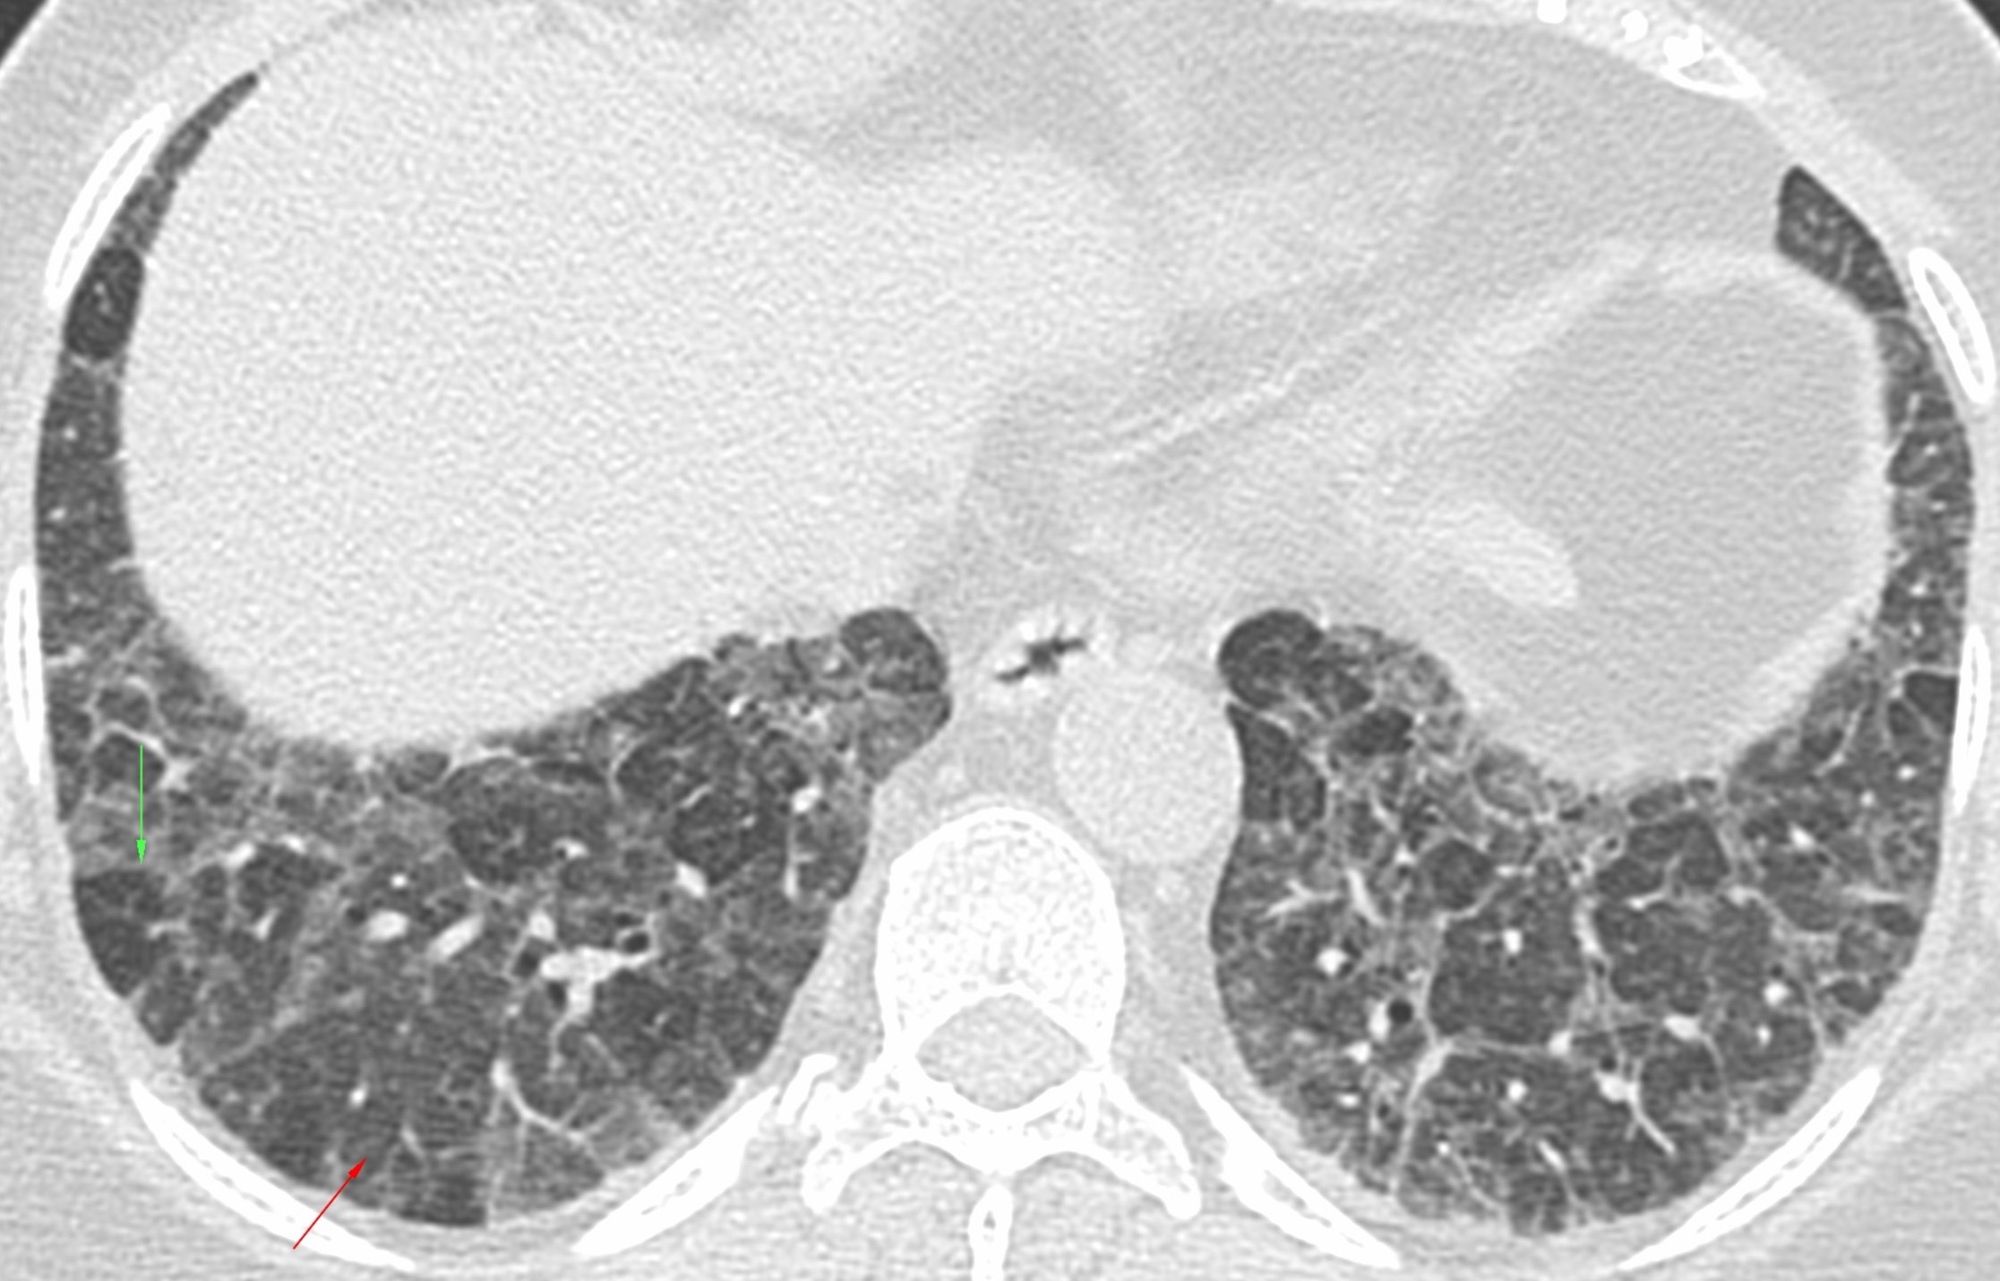

Figure 3 from Hypersensitivity pneumonitis imaging findings on high Wind Instrument Hypersensitivity Pneumonitis Playing a wind instrument is an increasingly reported cause of hypersensitivity pneumonitis. hypersensitivity pneumonitis is triggered by the immune system's response to an inhaled environmental. recently, clinicians identified a new type of ‘wind instrument’ as a potential cause of hp if it is inadequately cleaned and remains. hypersensitivity pneumonitis (hp) is a complex pulmonary disorder mediated by. Wind Instrument Hypersensitivity Pneumonitis.

Hypersensitivity Pneumonitis Spectrum of HighResolution CT and Wind Instrument Hypersensitivity Pneumonitis Playing a wind instrument is an increasingly reported cause of hypersensitivity pneumonitis. king calls playing wind instruments a “risk factor” for hypersensitivity pneumonitis. we report two cases of hp caused by molds and atypical mycobacteria isolated from wind. As described in the above. hypersensitivity pneumonitis (hp) is a complex pulmonary disorder mediated by the immune system and.. Wind Instrument Hypersensitivity Pneumonitis.